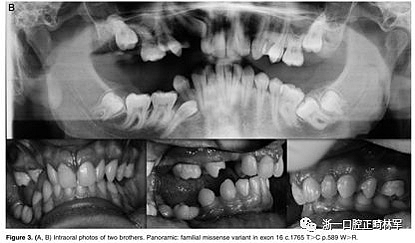

正畸文獻(xiàn)閱讀--原發(fā)性萌出失?。夯旌涎懒械呐R床和遺傳學(xué)研究

正畸文獻(xiàn)閱讀--原發(fā)性萌出失敗:混合牙列的臨床和遺傳學(xué)研究

圖3.(A,B)兩兄弟的口內(nèi)照片。全景:外顯子16中的家族錯(cuò)義變體c.1765 T>C p.589 W>R

屬于2號(hào)家庭的小女兒(2:2)表現(xiàn)出更復(fù)雜的臨床表現(xiàn),缺乏永久性以及暫時(shí)性系列和囊性結(jié)構(gòu)元素的萌出(圖3A,B)。在哥哥(II:1;圖3A,B)中發(fā)現(xiàn)由于包括多顆恒牙的嚴(yán)重的雙側(cè)后牙開合。最后,患者II:1和II:2的母親表現(xiàn)出雙側(cè)上頜第一磨牙和下磨牙的包埋。發(fā)現(xiàn)前磨牙層面沒有咬合接觸(圖3A,B)。